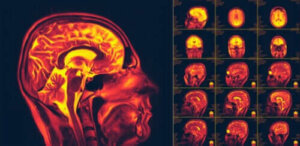

بعد ذلك، بدؤوا في اللجوء لبعض فحوصات التصوير والمحاكاة لإثبات لدونة المخ العصبية. ولا يزال العلماء يبحثون في جميع جوانب هذه الظاهرة.